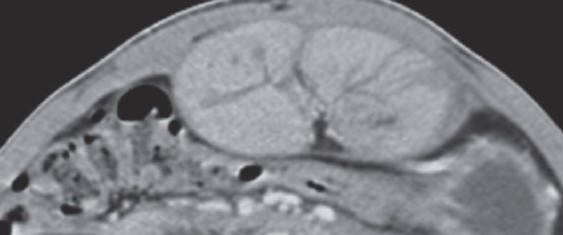

Abdominal CT. Abdominal "cocoon". Encapsulated bowel loops (Courtesy Dr. V. Penopoulos)